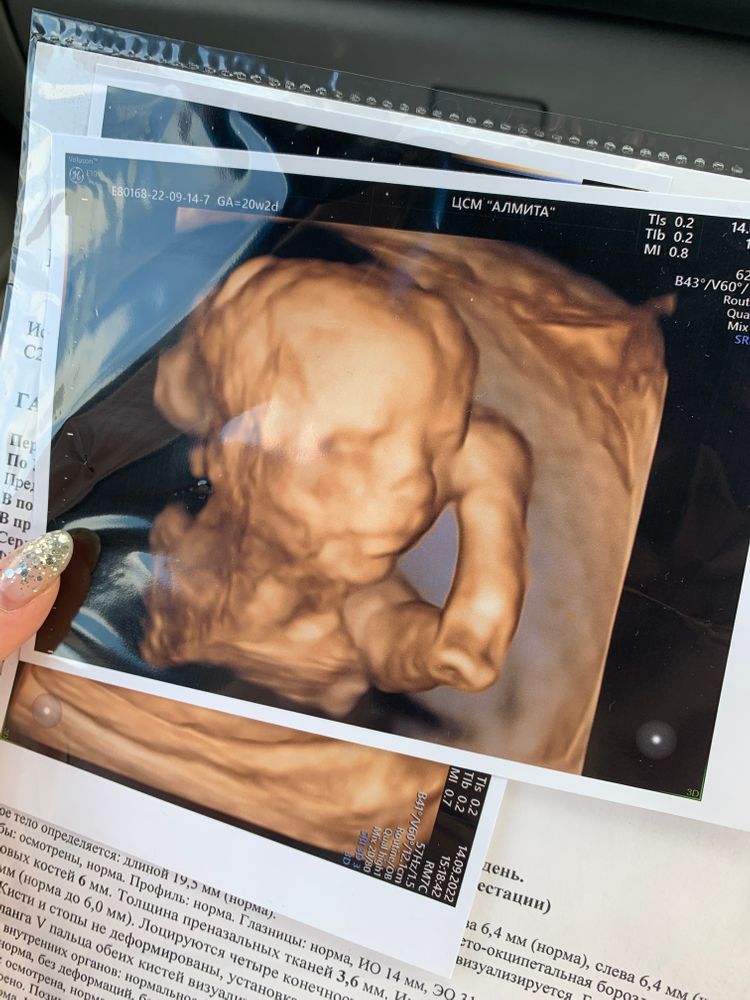

2- ой Скрининг 20.2 недели 💓

Ну вот дождалась, ) очень сложно было сфоткаться , узи шло 35 минут . Все у нас отлично по всем критериям , дочка опережает на неделю по параметрам . На узи крутилась , сначала поперечно легла , потом тазово , на месте не сидит . Цервикальный канал 34.1мм, сказали все гуд, изначально был 36мм. По массе мы 336 гр.